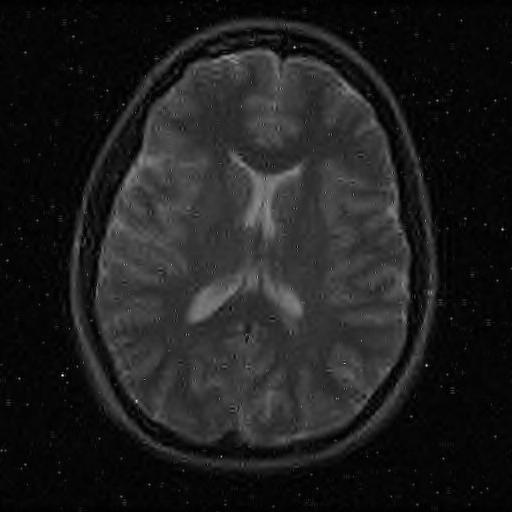

We illustrate our findings with numerical experiments, first consider various artificial setups in which we show that splitting a signal via local projections allows for accurate, stable, and robust estimation. We verify that by increasing the size of the fusion frame, a certain robustness to noise is also achieved. While the computational complexity remains relatively low, we achieve stronger recovery performance compared to usual single-device compressed sensing systems. We finally show how our techniques can be applied in various signal processing tasks such as Doppler signal denoising, natural scene scanning and reconstruction, and MR Image reconstruction. In these examples, we empirically verify that visually good reconstruction are obtained, even in highly undersampled and noisy regimes.

• [39] T. Zhang. Sparse recovery with orthogonal matching pursuit under rip. Information Theory, IEEE Transactions on, 57(9):6215–6221, 2011.